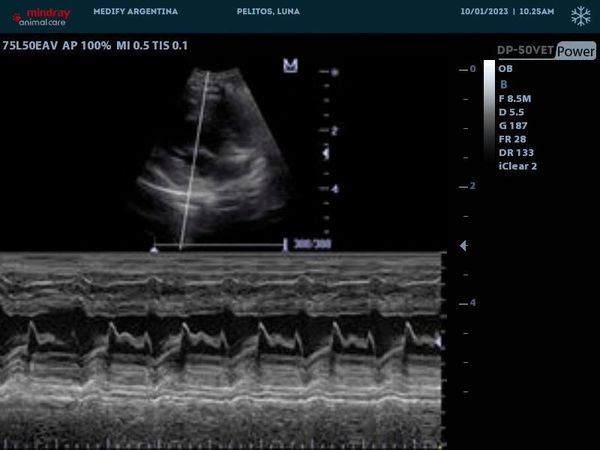

Proporciona información sobre la dirección y la velocidad del flujo sanguíneo en diferentes áreas del cuerpo del animal, lo que puede ayudar en el diagnóstico de condiciones vasculares y cardiacas.

DP50vet ofrece imágenes de alta resolución y claridad, permitiendo una visualización detallada de los tejidos y estructuras anatómicas en animales de diferentes tamaños y especies.